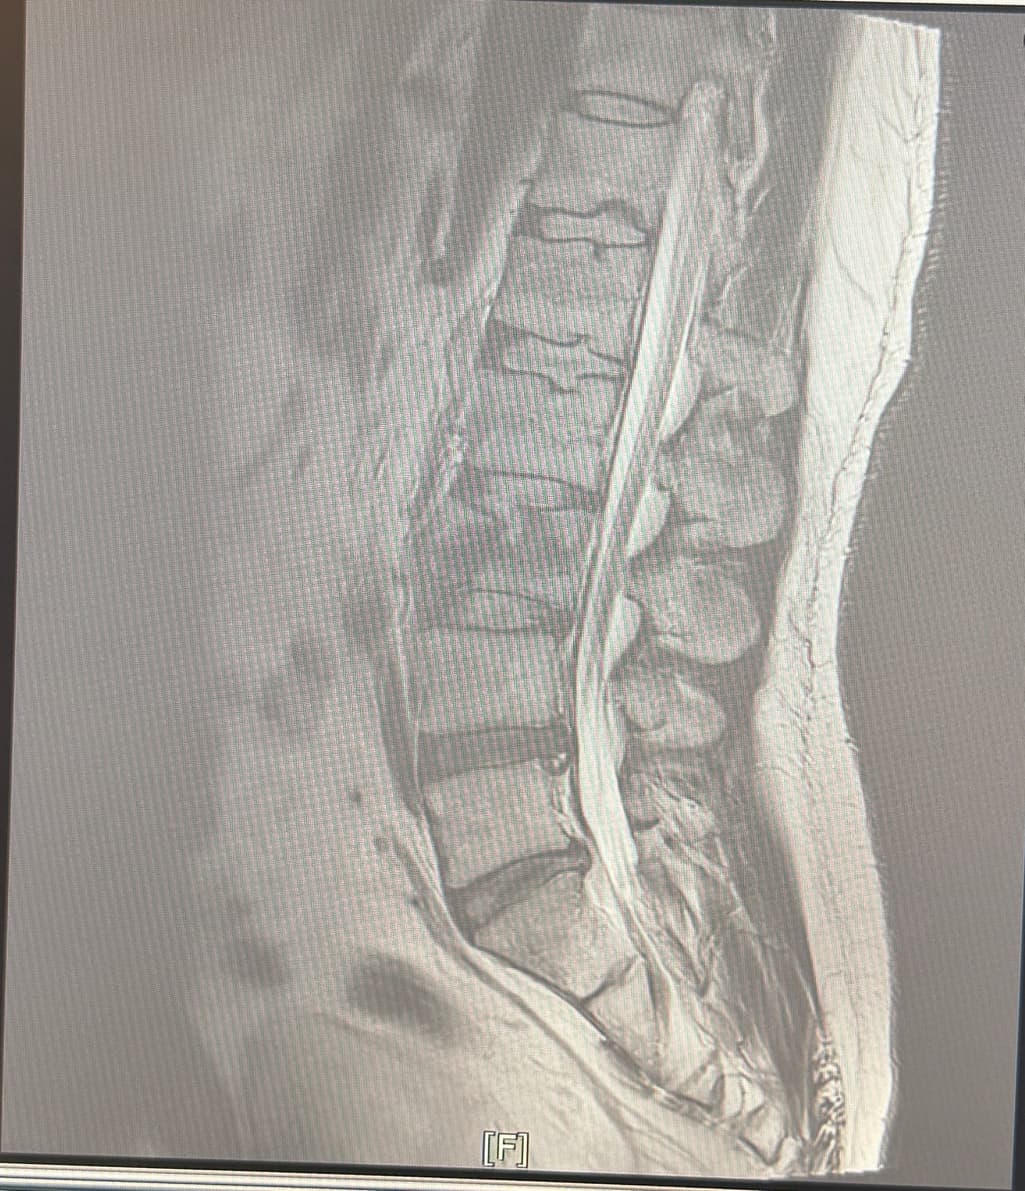

혹시 이건 무슨골절이라고하나요 ??

낙상으로인해 척추가 골절됐는데 세조각으로 조각났어요

제가 아직 누워있어서 면담은 못했지만 이런 골절도 아빡골절이라고하나요? 아님 다른 명칭이 있나요?

낙상으로 척추가 세 조각으로 부러졌다면 척추뼈의 골절은 압박골절이라고 하며 단순한 압박골절을 넘는 더 심한 형태일 가능성도 존재합니다.

압박 골절은 척추체 몸통이 위에서 눌리면서 찌그러지면서 발생하는 골절로 대개 한 조각처럼 부서지는게 특징이고 파열 골절은 척추가 여러조각으로 터지듯 골절되는 상태를 의미합니다.

분쇄골절은 2개 이상의 골전선에 의해 3개 이상의 골절편이 발생하는 것을 말하며

낙상으로 인하여 세조각으로 골절이 발생하였다면 분쇄골절이라고 합니다.

척추가 세 조각으로 부러졌다면 일반적으로 폭팔골절일 가능성이 높아요 압박골절보다 더 심한 형태로 뼛조각이 주변 신경을 압박할 수 있어 신경학적 증상 유무가 중요합니다.

압박골절 말하시는거 같습니다. 척추가 세 조각으로 골절된 경우, 압박골절(compression fracture) 또는 분쇄골절(comminuted fracture)로 분류될 수 있습니다. 압박골절은 척추뼈가 압력에 의해 납작해지거나 쪼개지는 경우를 말하며, 분쇄골절은 뼈가 여러 조각으로 부서지는 경우에 해당되죠. 특히, 낙상으로 인해 골절이 일어난 경우, 충격의 강도에 따라 이런 형태의 골절이 발생할 수 있어요

만약 척추의 골절 부위가 세 조각 이상으로 분리되었다면 분쇄골절이 더 적합한 명칭일 수 있습니다. 이런 골절은 치료 과정에서 신경 손상이나 다른 합병증이 발생할 수 있기 때문에 정확한 진단과 적절한 치료가 중요합니다.